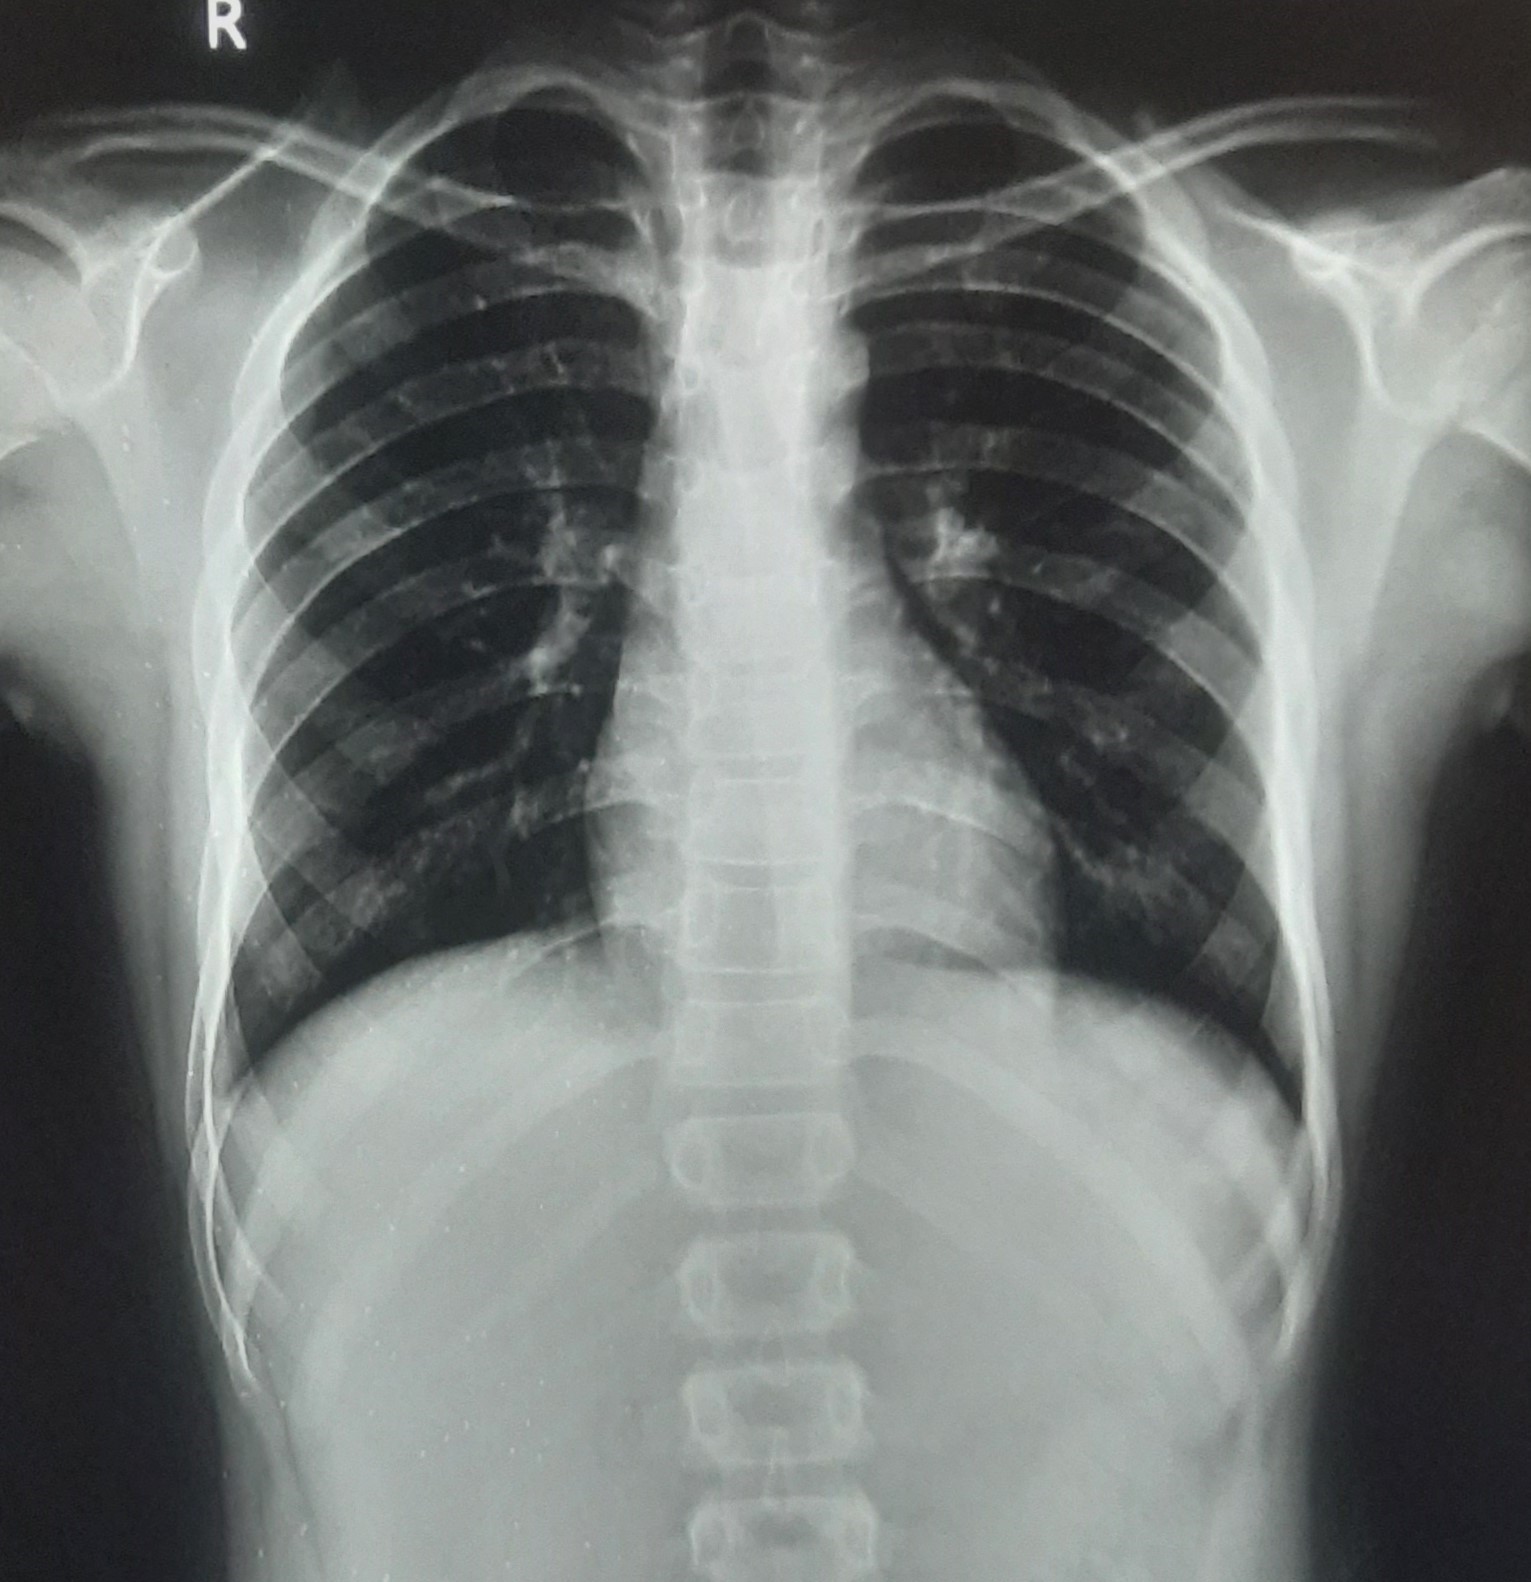

| 212 | IGGMC, Nagpur, Nagpur | P2 | 29-4260 | MALTI REVATKAR | Consent taken on Paper | 32 Yrs. |

Provisional Diag : B/L INFILTRATION ? PTB

Final Diag : Microbiologically Confirmed Pulmonary Tuberculosis |

TB Case (Confirmed) | B/L INFILTRATION | Abnormality visible on x-ray |

View |